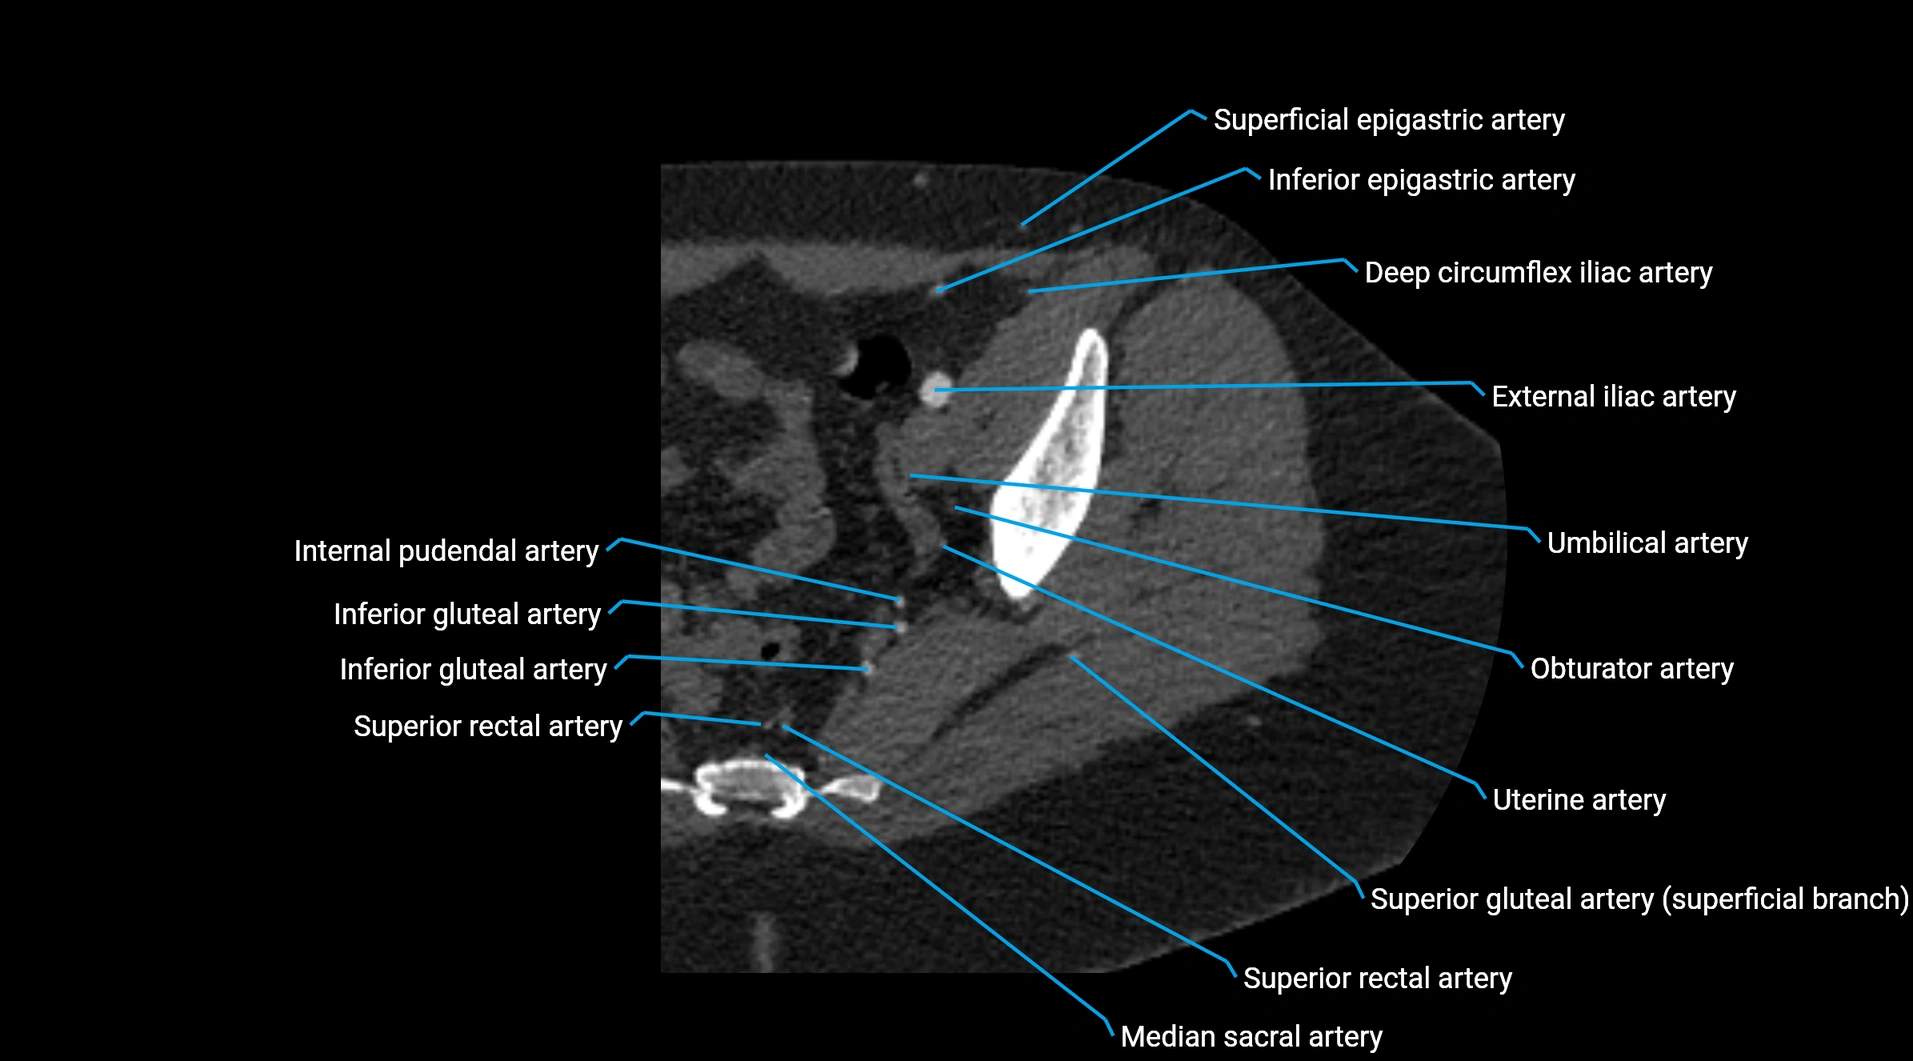

CT images

image